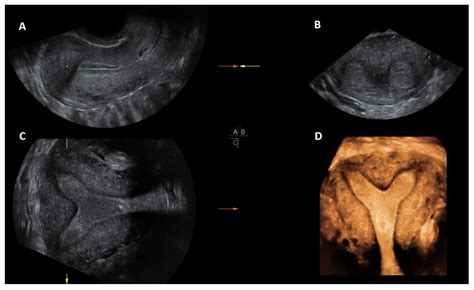

Uterus didelphys, commonly referred to as a “double uterus,” is a congenital condition where the uterus is present as two separate organs, each with its own cervix and often a duplicated vagina. This anomaly occurs during fetal development when the Müllerian ducts—the structures that eventually form the female reproductive tract—fail to fuse together completely. Instead of forming a single, pear-shaped uterus, they develop into two separate, smaller uterine cavities.

Physicians use advanced imaging to confirm the diagnosis. If you are looking at Didelphic Uterus Images for reference, you will notice the clear separation of the two uterine horns. Common diagnostic tools include:

When analyzing Didelphic Uterus Images in a medical context, notice how the dual cervixes are positioned. This is a critical detail for healthcare providers during cervical cancer screenings (Pap smears) or during labor and delivery, as each side needs to be assessed independently.